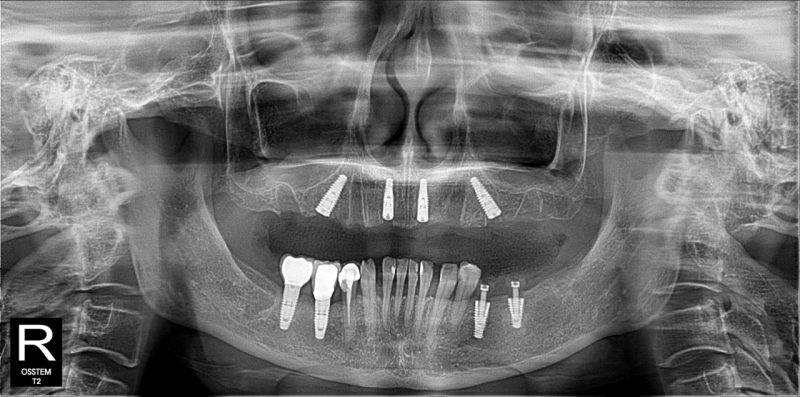

Sau khi đánh giá kỹ lưỡng tình trạng răng miệng, đội ngũ bác sĩ chuyên môn đã xây dựng phác đồ điều trị: Cắm All On 4 hàm trên và 2 trụ Implant đơn lẻ hàm dưới R35, R36.